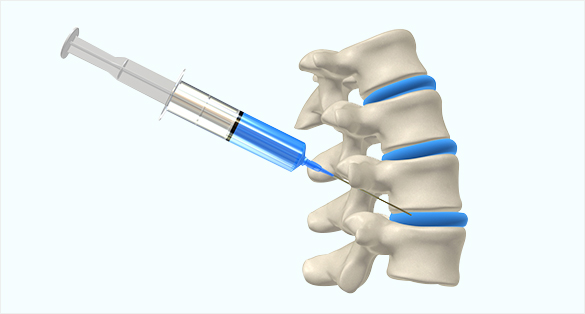

신경성형술

척추관 안쪽으로 카테타를 넣어서 신경에 염증제거, 부종감소,유착박리를 하는 특수 시술입니다.

디스크를 효과적으로 치료할 수 있습니다.